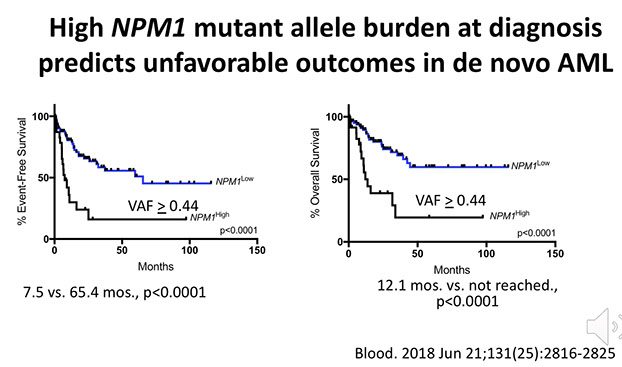

- Acute myeloid leukemia with mutated NPM1